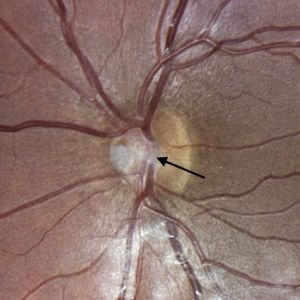

Bergmeister papillae can be observed with ophthalmoscopy and fundus photography (Figure 3), but they are more likely to be identified through optical coherence tomography (OCT) (Figure 1).[6][7][8] Visualization reveals a cluster of veil-like glial or fibroglial tissue emerging anteriorly, centrally, and nasally from the optic nerve head.[9][10][11] Presence of papillae can influence the size of the optic nerve head cup.[4] Bergmeister papillae can be unilateral or bilateral.[7]